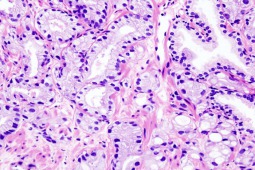

Wysokie stężenie cholesterolu jest znanym czynnikiem ryzyka chorób sercowo-naczyniowych, ale znacznie mniej wiadomo o jego wpływie na ryzyko rozwoju nowotworów. Wcześniejsze badania na zwierzętach wykazały już, że podawanie statyn z powodu hipercholesterolemii może zmniejszać ryzyko raka piersi, a celem badaczy była ocena wpływu wysokiego stężenia cholesterolu i jego leczenia na zgony związane z chorobami nowotworowymi.

Pomiędzy styczniem 2000 a marcem 2013 roku zebrano anonimowe informacje dotyczące chorych, u których rozpoznano raka płuca, piersi, prostaty i jelita. Dane dotyczące zgonów pochodziły z Office for National Statistics. Analizując dane badacze zauważyli, że chorzy z rozpoznaniem hipercholesterolemii i jednego z czterech nowotworów mieli mniejsze ryzyko zgonu z powodu choroby nowotworowej. Badacze wysnuli również hipotezę, że do zmniejszenia tego ryzyka prowadzi raczej leczenie statynami niż sam poziom cholesterolu. Skorygowali również wyniki o inne czynniki ryzyka, takie jak wiek, płeć, pochodzenie, i inne częste przyczyny zgonu

Wykazano, że podwyższone stężenie cholesterolu zmniejsza ryzyko zgonu z powodu raka płuca o 22 proc., z powodu raka piersi o 43 proc., z powody raka prostaty o 47 proc. i o 30 proc. z powodu raka jelita.